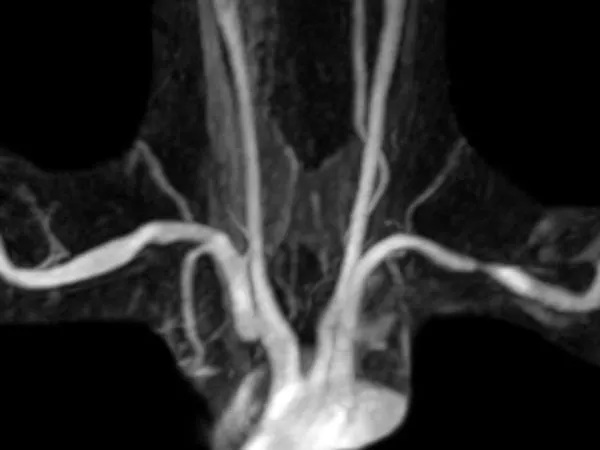

MR angiography is performed by injecting contrast into a peripheral vein, without an arterial catheter. MRA shows excellent arterial detail while eliminating most other structures, including bones. It requires no radiation. If used in conjunction with MRI, superb soft tissue detail is available. Excellent depiction of fibrous bands, muscle anomalies, bones, and the brachial plexus is possible with MRI.

This interactive media demonstrates magnetic resonance angiography (MRA) images in two different patients. One patient has a normal MRA. The other patient has compression of each subclavian artery. Note that the structures that cause this compression are not visible on MRA alone.